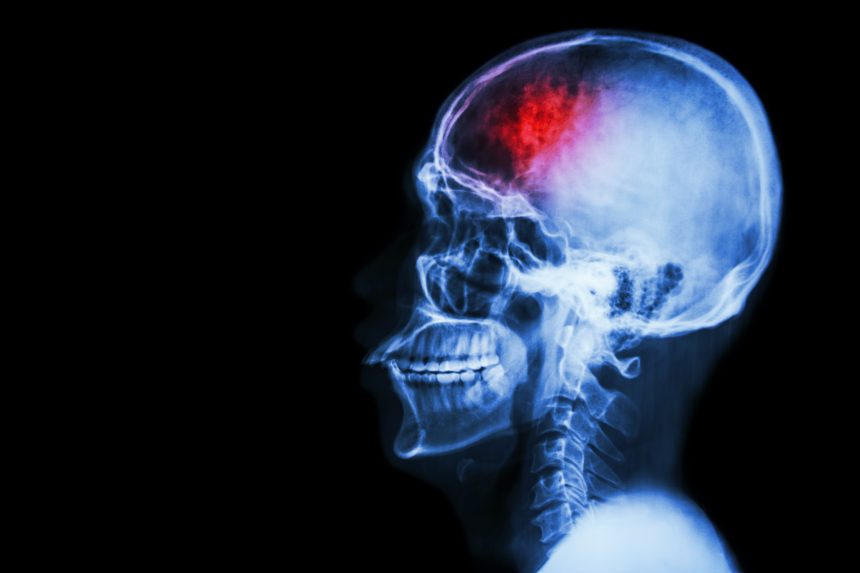

מה זה שבץ או אירוע מוחי?

שבץ מוחי (שנקרא גם "אירוע מוחי") הוא אירוע פתאומי שגורם נזק למוח.

איסכמיה מוחית– זהו מצב שבו קריש דם חוסם את אחד העורקים שמובילים את הדם למוח. כתוצאה מכך, כלי הדם נסגר ובגלל חוסר זרימת הדם למוח מתפתחת פגיעה עצבית.

דימום ספונטני מוחי – נחשב לנדיר יותר ונגרם מדליפה של אחד מכלי הדם במוח שמובילה לדימום יתר. ובכך יכול לגרום לנזק.